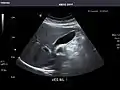

Spleen: Normal in size.

Spleen